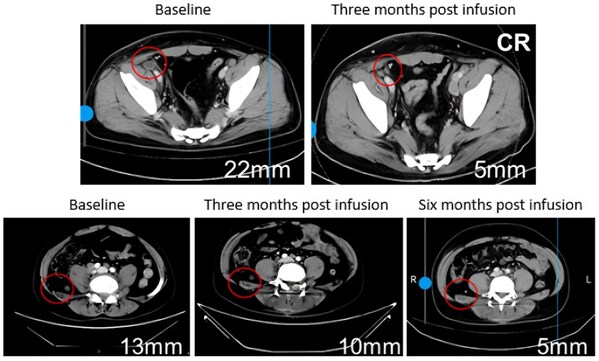

In terms of efficacy,disease control and response rates exhibited a clear dose-dependent relationship. Higher doses led to more significant effects,with 75% of patients experiencing a sustained reduction in tumor burden and diminished metabolic activity,and several lesions achieving complete response (CR) with 100% tumor reduction.

Patients treated with BRG01 have shown a progression-free survival exceeding six months post-infusion, demonstrating significantly extended antitumor effects compared to the current standard treatment,checkpoint inhibitors like PD-1 antibodies.